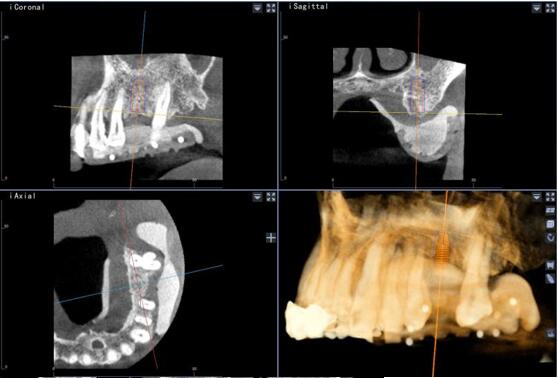

術(shù)前種植體規(guī)劃

術(shù)中實(shí)時(shí)種植導(dǎo)航

術(shù)后精度驗(yàn)證

種植體類 型植入點(diǎn) 末 端角 度

26 計(jì)劃<->實(shí)際 0.88 0.96 2.68